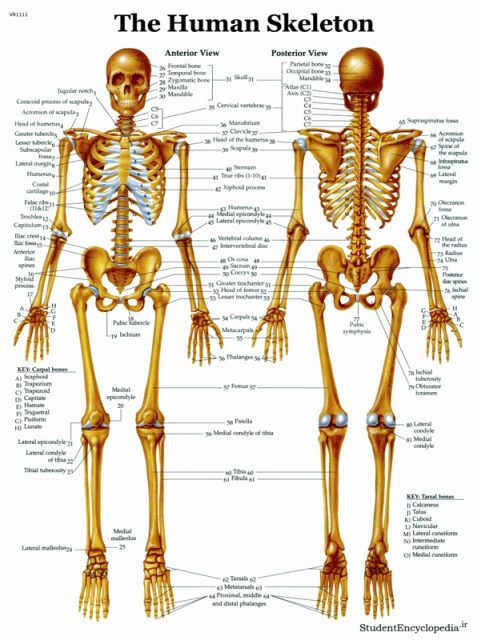

عکس اسکلت بدن انسان. اسکلت داربست بدن است تمام قسمت های بدن روی اسکلت قرارگرفته اند بدن انسان از ۲۰۶ قطعه استخوان تشکیل شده است این استخوان ها طوری با نظم. هر قسمت بدن از انواع مختلف سلول تشکیل شده است. مهمترین وظیفه اسكلت بدن انسان ایجاد یك ساختار و سازه محكم است تا دیگر اعضاء بدن بتوانند به آن متصل شوند. سازه و چهارچوب اصلی بدن.

اسکلت داربست بدن است تمام قسمت های بدن روی اسکلت قرارگرفته اند بدن انسان از ۲۰۶ قطعه استخوان تشکیل شده است این استخوان ها طوری با نظم کنار هم قرار گرفته اند که انسان را قادر می سازد حرکات دقیقی داشته باشد. بدون اسكلت بدن مانند كرم شل و نرم است و این نوع شكل بندی نمیتواند. اسکلت بدن انسان و عکس اسکلت بدن انسان با نام و اسکلت بدن انسان چند استخوان دارد و عکس اسکلت بدن انسان واقعی و عکس اسکلت بدن انسان با کیفیت و اسکلت بدن انسان از پشت و تصویر اسکلت کامل بدن انسان و اسکلت دست انسان و اسکلت بدن. معرفی بدن انسان اسکلیت.

اسکلت داربست بدن است تمام قسمت های بدن روی اسکلت قرارگرفته اند بدن انسان از ۲۰۶ قطعه استخوان تشکیل شده است این استخوان ها طوری با نظم کنار هم قرار گرفته اند که انسان را قادر می سازد حرکات دقیقی داشته باشد. استخوان یک نسج بسیار محکم است زیرا در ترکیب آن منرالها مانند کلسیم و دیگر وجود. اسکلت داربست بدن است تمام قسمت های بدن روی اسکلت قرارگرفته اند بدن انسان از ۲۰۶ قطعه استخوان تشکیل شده است این استخوان ها طوری با نظم کنار هم قرار گرفته اند که انسان را قادر می سازد حرکات دقیقی داشته باشد. آناتومی سه بعدی بدن انسان عکس گرافی بدن امعاء و احشاء بدن آناتومی سه بعدی بدن انسان عکس گرافی بدن امعاء و احشاء بدن قلب کبد روده.

اسکلت داربست بدن است تمام قسمت های بدن روی اسکلت قرارگرفته اند بدن انسان از 206 قطعه استخوان تشکیل شده است این استخوان ها طوری با نظم کنار هم قرار گرفته اند که انسان را قادر می سازد حرکات دقیقی داشته باشد. اسكلت به بدن شكل میدهد. عکس اسکلت بدن انسان زن و مرد آناتومی ساتین 16 سپتامبر 2017.